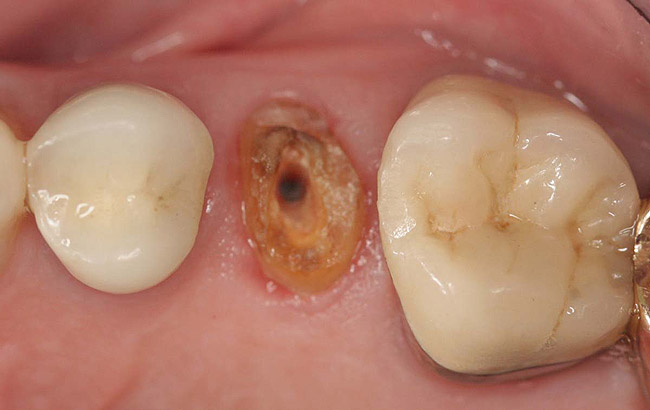

Case 2

A Class IIIN maxillary left second molar required restoration (Figure 6). Four canals, a chamber space, and little cross section of tooth structure were in the gingival third. Gutta-percha was removed with a Peeso reamer supplied in the C-1 kit. The canal was shaped with a bur in the kit, which was the same size as the corresponding post (Figure 7). The tooth structure was bonded with Brush & Bond™ (Parkell, www.parkell.com), and then the resin cement was spun into the canal with a lenticulo spiral. A C-1 white post was placed in the palatal canals (Figure 8). The C-1 White Post is a fiber-reinforced composite post, which flexes at the same rate as dentin to minimize root stresses.

Figure 8  Second molar after post cementing.

Figure 8

Figure 9  Cure core material placed without a matrix.

Figure 9

Figure 10  Final tooth preparation to accept a PFM crown.

Figure 10

Figure 11  Final porcelain-fused-to-metal crown.

Figure 11